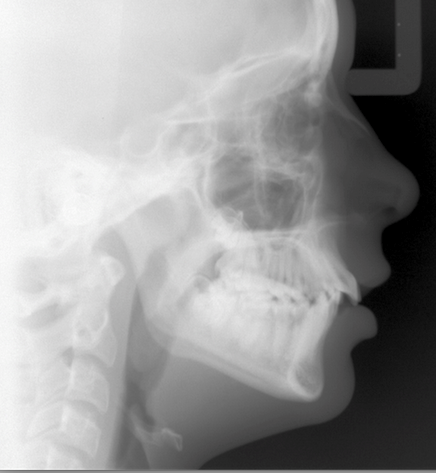

Class II malocclusion patterns will usually be a combination of skeletal and dental components. Mandibular deficiency and maxillary protrusion are common elements of Class II growth patterns. (Figure 1) Decisions on referral and treatment timing can be refined with the three considerations that will be discussed here. The result can be an increased confidence in contributing to a successful and stable outcome.

Growth charts with the average time for peak growth can be a start to guide us.1 Family and parental growth patterns and recent growth of the patient can get us closer to accurately predicting the circumpubertal growth range. Growth charts show females peak rate of growth is during the years of 11 to 13. For males, the peak growth range is age 14 to 16. Cephalometric images using the cervical vertebral maturation (CVM) have also been reported to aid in determining the time of the mandibular growth spurt.2 CVMS 2 and CVMS 3 are correlated with the mandibular growth spurt. Given these guidelines, if a female patient needs mandibular advancement with growth modification, a successful outcome is more predictable during the peak rate of mandibular growth.